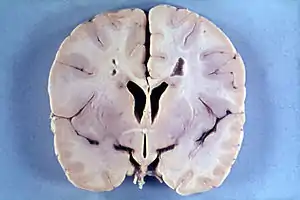

Мегаленцефалія та гемімегаленцефалія

Мегаленцефалія — це порушення розвитку при якому мозок має аномально великий розмір. Середня вага мозку на 2,5 стандартні відхилення перевищує середнє значення загальної сукупності[10]. Гемімегаленцефалія — надзвичайно рідкісна форма макроцефалії, що характеризується нерівномірним розвитком півкуль мозку (половина мозку більша за іншу)[11].